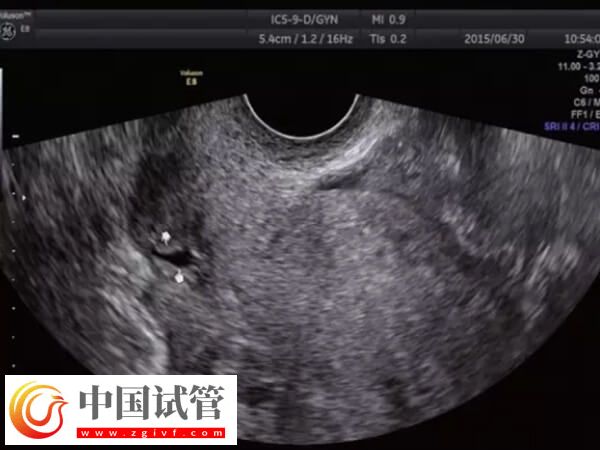

子宮憩室一般也叫剖宮產(chǎn)切口憩室或者子宮切口瘢痕缺損,主要是因?yàn)槠蕦m產(chǎn)手術(shù)遺留的刀口組織恢復(fù)不佳,從而造成的一個(gè)子宮凹陷空間。女性出現(xiàn)子宮憩室時(shí),通過(guò)試管嬰兒技術(shù)助孕怎么樣,可以參考下列內(nèi)容:

不過(guò)因個(gè)體之間存在較大的差異,所以子宮憩室能否做試管嬰兒,還需要根據(jù)患者的年齡、癥狀、既往妊娠并發(fā)癥、子宮腔的狀態(tài)、憩室的大小、疤痕處的肌層厚度等多方面進(jìn)行判斷,患者可以直接前往醫(yī)院咨詢(xún)相關(guān)醫(yī)生即可。